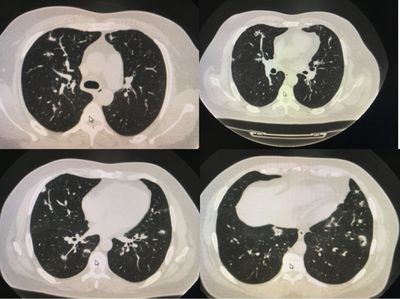

6、双肺多发磨玻璃结节是怎么回事?要怎样治疗

双肺多发毛玻璃结节是一种常见的肺部疾病,由多种原因引起,损害了患者的肺部健康,给患者带来困扰,引起咳嗽症状。朋友们一定要警惕这种疾病的发生,一旦发生需要积极治疗,充分了解这种疾病的治疗措施。大多数肺部有玻璃结节的患者是通过体检发现的,没有任何症状。这种肺部的小结节和体表的肿瘤不一样。当胸膜未受累时,由于缺乏相应的感觉神经分布,这些结节一般无症状。

一旦有磨玻璃结节,就要正视,不要太惊慌,也不要当真。再来看看双肺多发毛玻璃结节的治疗措施。近年来,双肺多发磨玻璃结节越来越常见,严重损害患者肺部,并引起异常呼吸症状,给患者带来更多困扰。要提高警惕,身体患病后需要积极治疗。肺部患病后,可以用中药方剂,如麻石转阴,可以清气止咳平喘。药物为麻黄、莱菔子、半夏。